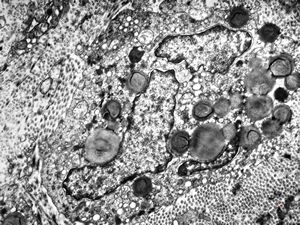

F, 24y. | molluscum contagiosum … virions

F, 24y. | molluscum contagiosum

F, 7y. | molluscum contagiosum … virions